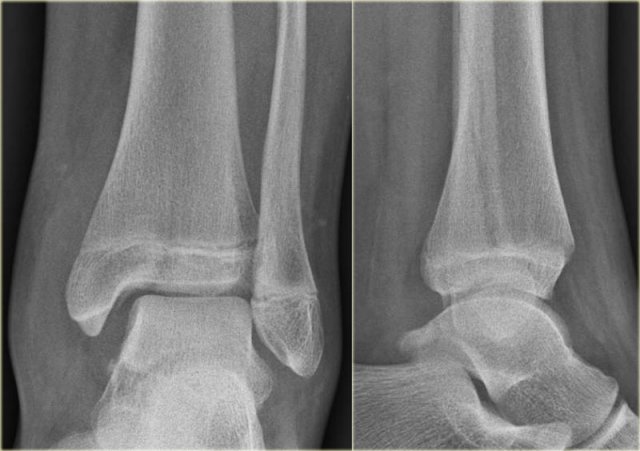

The images show an obvious Weber B fracture.

On the AP-view the linear lucency is the clue to a tertius fracture (red arrow).

It results from subtle malalignment of the fracture fragment.

Likewise in some cases malalignment can result in a linear density.

Trimalleolar Weber B fracture Trimalleolar Weber B fracture

In this case there is a Weber B fracture with avulsion of the medial malleolus.

The bright line on the AP-view indicates a large tertius fracture fragment.

This tertius fracture can also be seen on the lateral view, but in many cases we need all the information of both the lateral and AP-view to diagnose a tertius fracture.